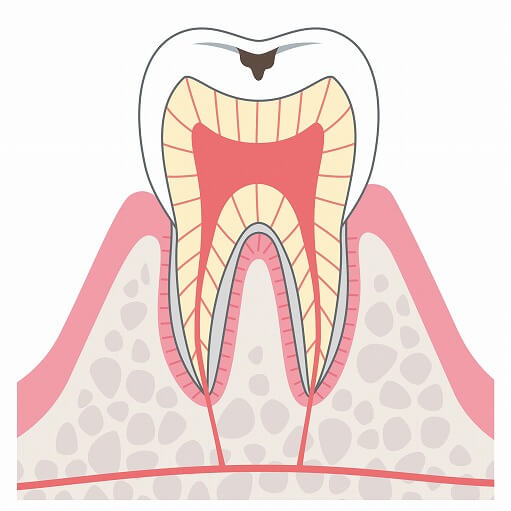

C0

痛みがなく自覚症状も見られずむし歯の治療としてフッ素塗布やブラッシング、予防治療をで問題ありません。

痛みがなく自覚症状も見られずむし歯の治療としてフッ素塗布やブラッシング、予防治療をで問題ありません。

このときに歯科医院に通うことで歯を抜かない・削らないで長くご自身の歯を大切に使うことができます。